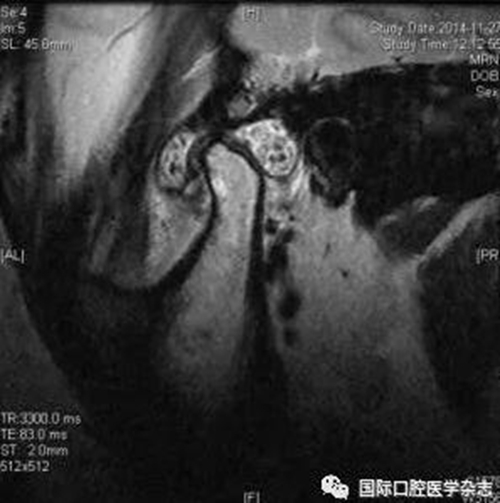

(2)不可復性關節(jié)盤前移位(圖1):多見于青壯年,往往與社會心理因素、牙合關系異常、代謝因素、偏側咀嚼、夜磨牙及不良習慣等因素相關。張口運動時,受髁突擠壓變形的關節(jié)盤不能復位;臨床有典型的關節(jié)彈響病史,進而彈響消失,出現(xiàn)開口受限,開口時下頜偏患側及關節(jié)區(qū)疼痛。測量被動開口度時,開口度不能增大。輔助檢查中,錐形束CT顯示關節(jié)前間隙增寬,造影片或核磁共振成像(magnetic resonance imaging,MRI)顯示不可復性關節(jié)盤前移位。

圖 1 不可復性關節(jié)盤前移位